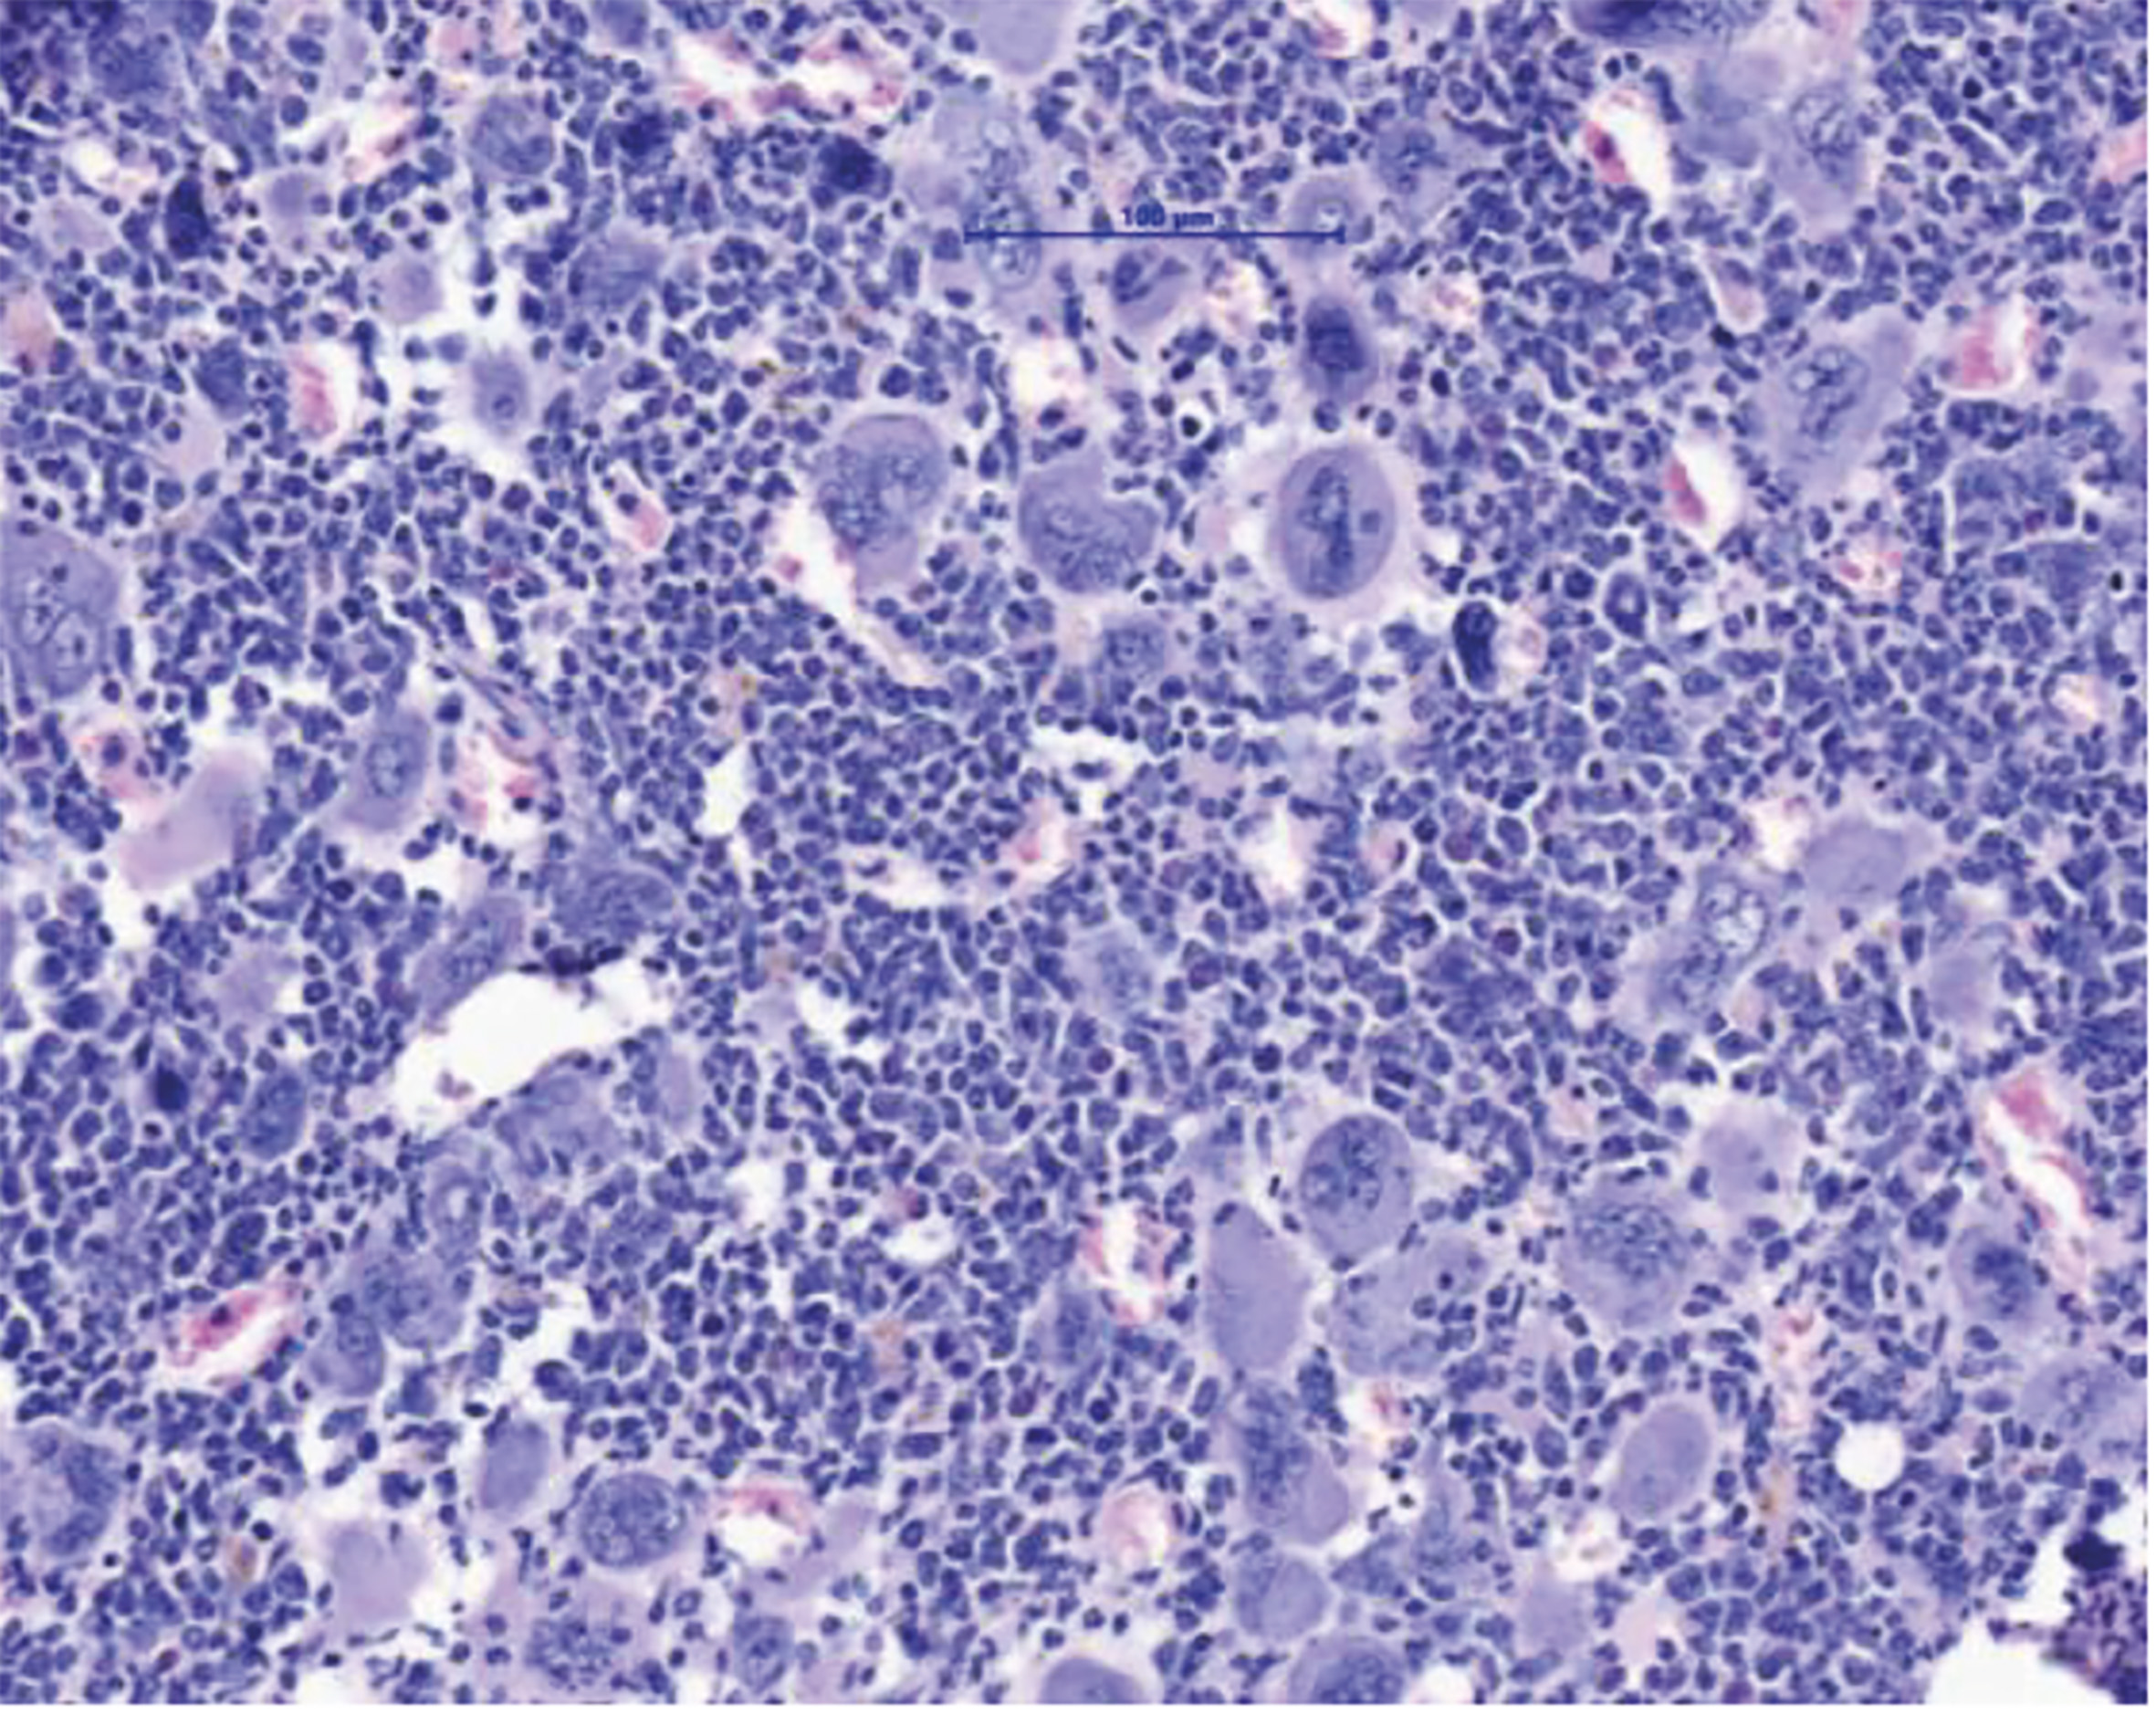

MPN sind durch eine Expansion des blutbildenden Systems im Knochenmark charakterisiert. Dies führt zum Anstieg verschiedener Zellreihen und im Endzustand dann zur Knochenmarksvernarbung und auch akuten Leukämie. (Grafik: MUI/Univ-Klinik für Innere Medizin V)

Innsbruck, Bonn am 2.12.2025: Myeloproliferative Neoplasien (MPN) sind Blutkrebserkrankungen, die durch eine Überproduktion von Blutzellen gekennzeichnet ist. Diese Erkrankungen treten in der Regel ab einem Alter von 60+ Jahren auf und können über lange Zeit gut kontrolliert werden. Gefährlich werden MPN vor allem nach dem Übergang in eine Myelofibrose – eine lebensbedrohliche Vernarbung des Knochenmarks. Eine allogene Stammzelltransplantation bietet für die betroffenen Patient:innen bis heute die einzige Aussicht auf Heilung. „Wir brauchen dringend neue Therapiekonzepte. Eine Stammzell-Transplantation ist für viele Patient:innen aufgrund ihres hohen Alters oder wegen Begleiterkrankungen mit zu hohen Risiken verbunden“, erklärt Dominik Wolf, Direktor der Univ.-Klinik für Innere Medizin V (Hämatologie und Onkologie) an der Medizinischen Universität Innsbruck, den Hintergrund einer soeben im Fachjournal Nature Communications hochrangig publizierten Forschungsarbeit, die er konzipiert und gemeinsam mit Lino Teichman und Miriam Körber vom UKBonn durchgeführt hat. „Wir zeigen in dieser Arbeit ein mögliches neues Therapiekonzept auf, das man klinisch weiterentwickeln sollte“, sagt Wolf, der gemeinsam mit Lino Teichmann als Letzt- und korrespondierender Autor firmiert. Den Wissenschafter:innen ist es gelungen, das NLRP3-Inflammason im Tiermodell zu hemmen und dadurch deutliche Verbesserungen des Krankheitsverlaufs zu erzielen: Die Knochenmarksvernarbung und die Milzvergrößerung bildeten sich zurück und das Blutbild verbesserte sich.